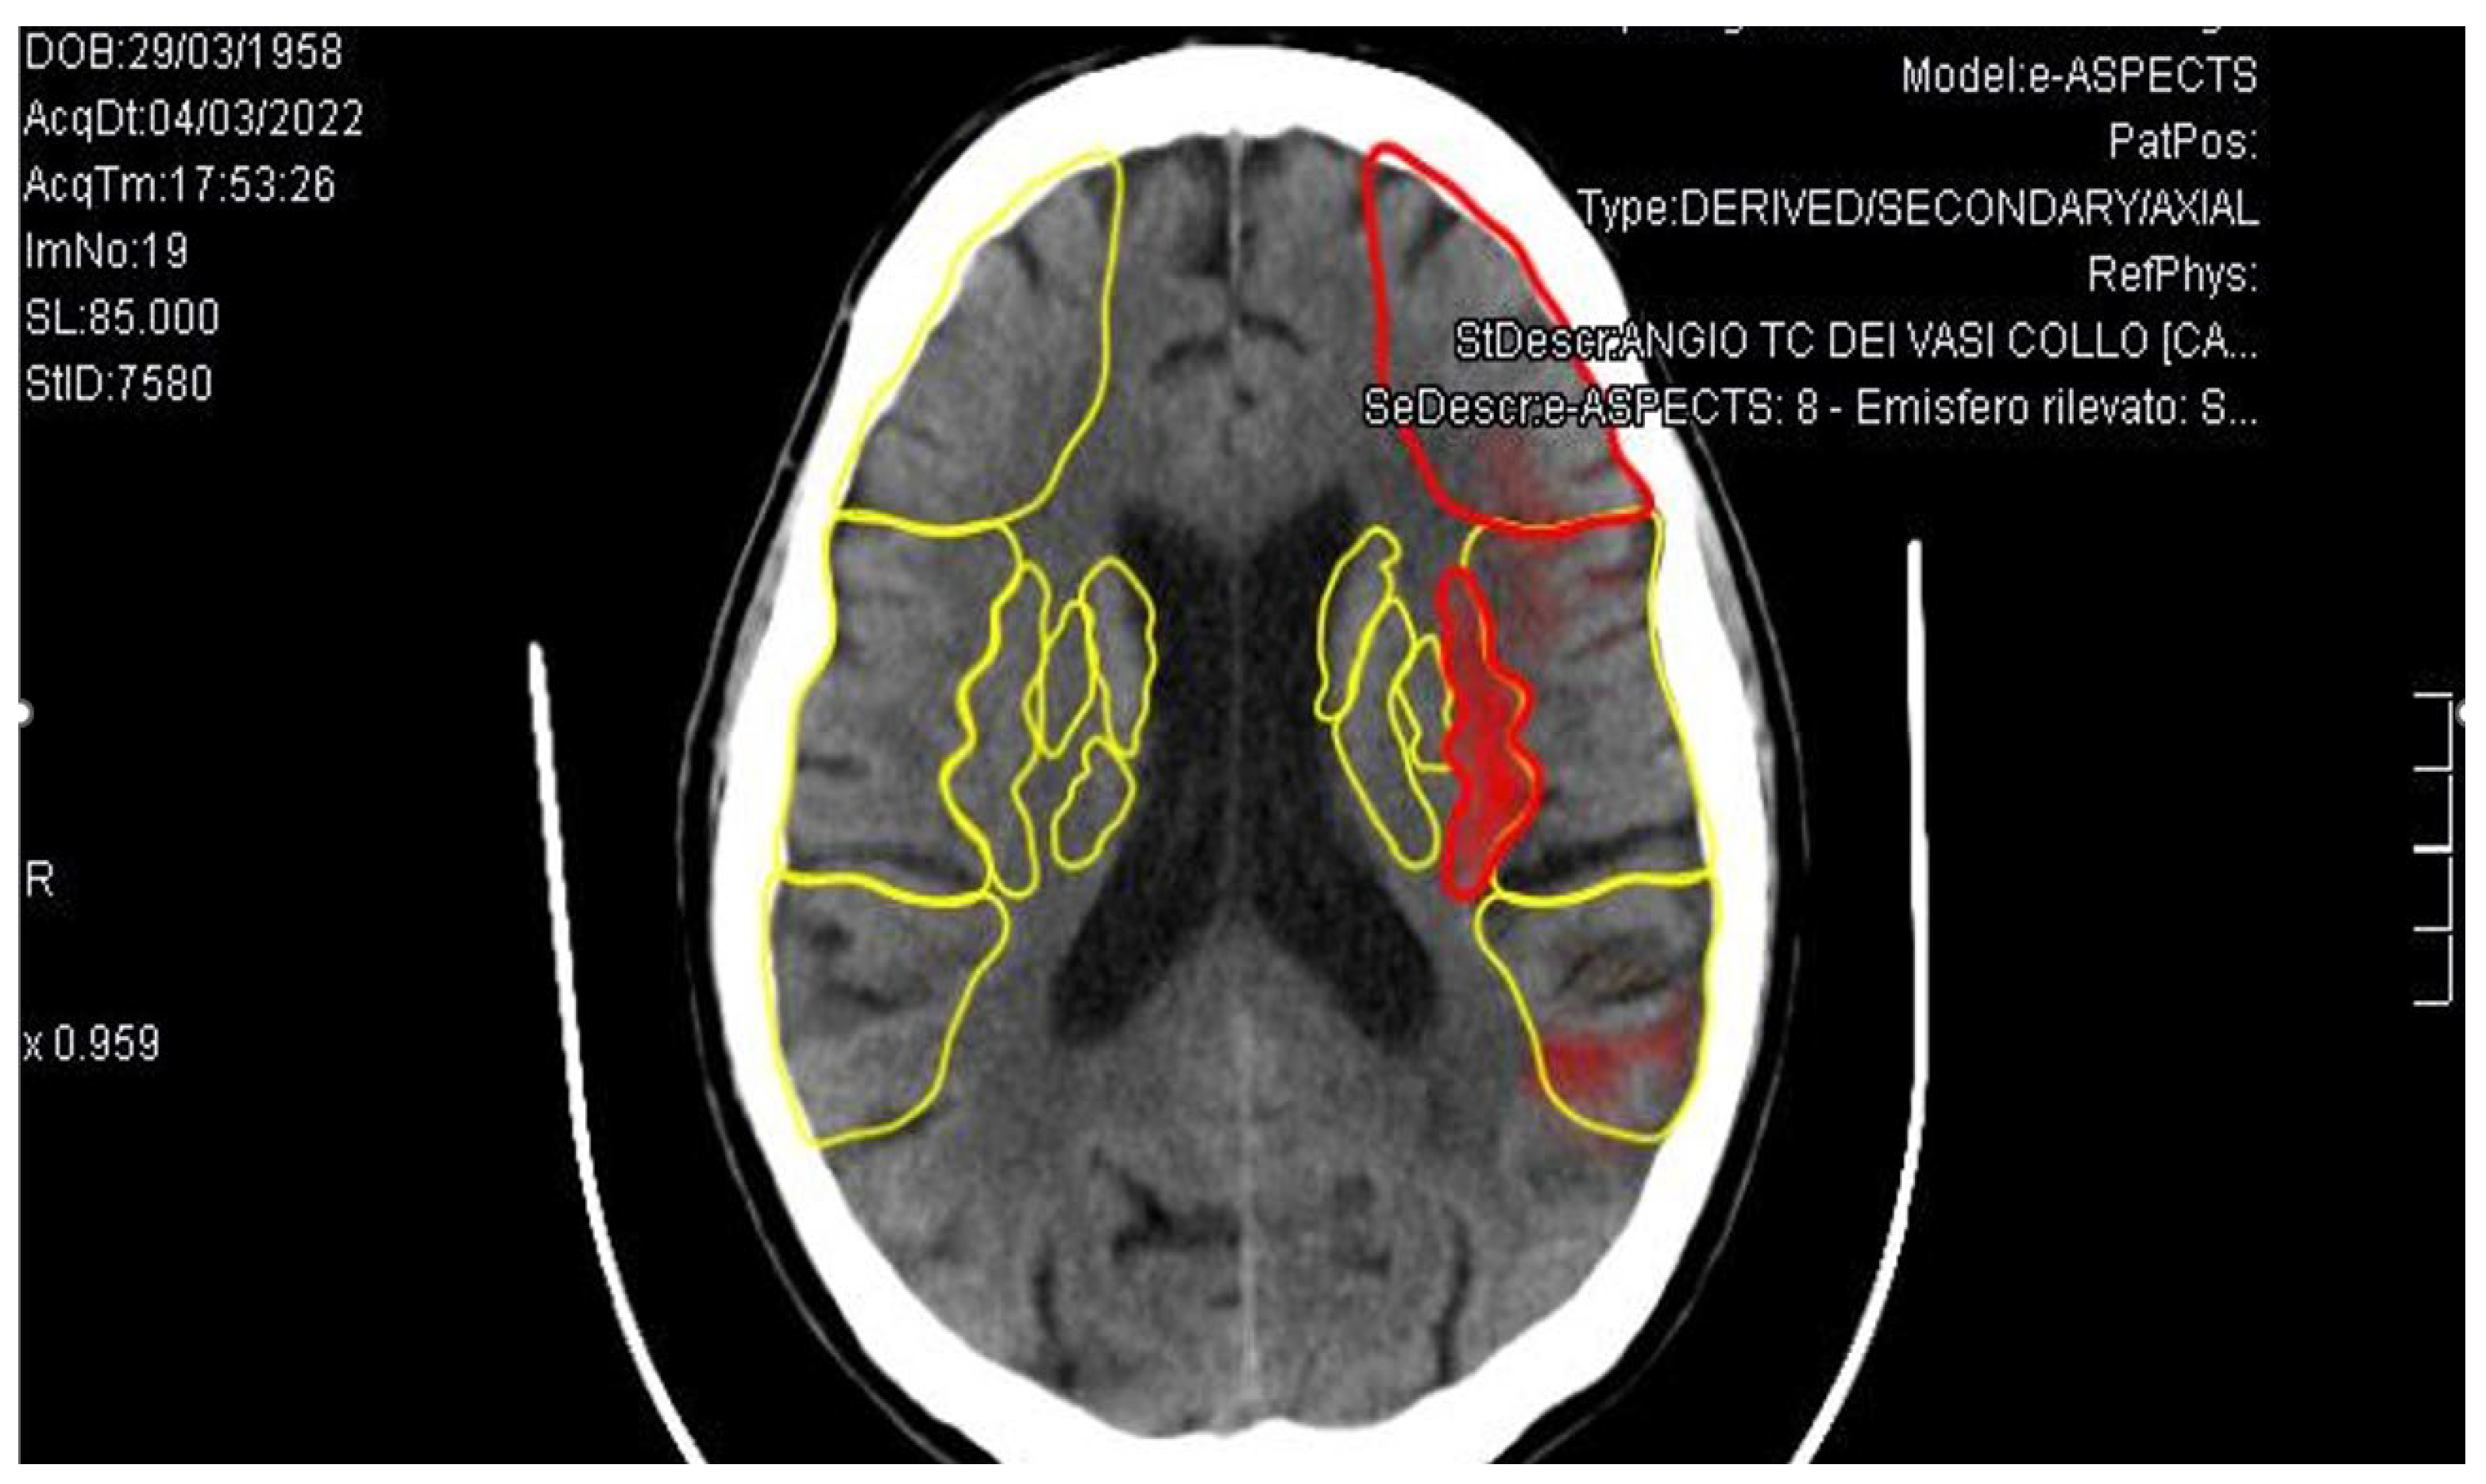

3. Case Report